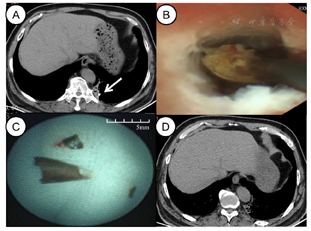

考虑病灶位于肺外周,在气管镜探查之前我们先根据肺CT进行手绘支气管导航绘图,即以圆圈代表支气管开口,在内部逐级绘制圆圈以代表下级支气管的走向,以此图来模拟支气管镜下视图,从而引导支气管镜顺利到达病灶。首先,我们阅读患者的薄层轴位CT,寻找病灶所在支气管,再回到所支配的段支气管,由段支气管逐步往病灶所在支气管滑动,在每一个支气管分叉处绘制示意图。如图2A所示,为与支气管镜视图的头-足位相对应,我们镜像翻转足-头位的肺CT图像,此时,CT图像上所显示的支气管的位置关系即与支气管镜视图一致。接着,如图2B所示,根据CT所显示的支气管分叉的位置关系及形态大小,从段支气管,也就是第3级支气管开始,逐层绘制支气管示意图。我们的手绘图提示CT上显示的高密度病灶在LB10ciiβ(左后基底段亚亚亚段)。

在全麻喉罩下,我们进行了气管镜探查。首先使用外径为5.9 mm的常规支气管镜(1TQ290,奥林巴斯),因LB10的狭窄,气管镜不能窥及远端。遂我们更换外径为2.8 mm,操作孔径为1.2 mm的超细支气管镜(UTB,BF-XP260,奥林巴斯)。在手绘支气管导航的引导下,我们顺利达到LB10ciiβ,发现异物坎顿于此,伴有明显的肉芽组织增生及大量脓性分泌物(图2C、D)。将气管镜固定于此处,经操作孔置入活检钳进行钳取,但是由于肉芽组织增生,管腔狭窄,异物钳无法张开。遂更换为常规支气管镜,交替使用高频电刀与活检钳从LB10近端至远端逐级清理肉芽组织。后再次更换超细支气管镜进入LB10ciiβ,以活检钳多次钳取,取出多片碎小辣椒屑,镜下探查未及明显异物后予以局部气道清理后结束治疗。

2021年5月10日复查肺CT显示左侧基底段的异物没有完全清理干净,剩下部分残屑被推向LB10ciiβ更远端(图3A)。2021年5月12日在全麻气管插管下,我们进行了第二次气管镜治疗。为避免活检钳将异物推向远端,我们使用了1.1 mm超细冷冻探头(ERBECRYO2,爱尔博)。如图3B所示,将超细支气管镜固定于LB10ciiβ病灶所在处,经操作孔置入超细冷冻探头,探头贴紧异物,冷冻4秒,冷冻结束后气管镜连同冷冻探头一起快速取出,经过2次冻取,剩余辣椒屑全部取出(图3C),术毕超细支气管镜探查未及异物。

2021年5月14日复查肺CT显示异物已完全取出,阻塞性肺炎改善(图3D)。